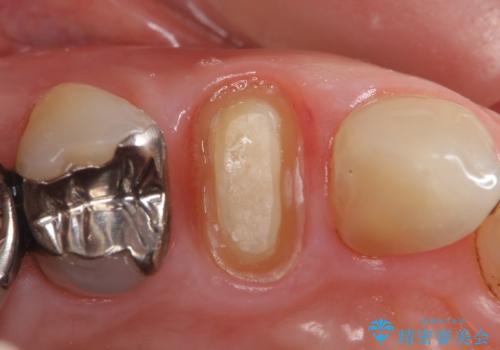

検査の結果持続痛も認めたため、虫歯除去後根管治療を行いました。

その後オールセラミッククラウン(エクセレント)による補綴を行いました。

前歯の補綴ではオールセラミッククラウンを希望される患者様が多いですが、オールセラミッククラウンの中でも、エコノミー、スタンダード、スペシャル、エクセレントとランクがあります。

その中でも特に審美性が高いのがスペシャル、エクセレントです。スペシャル、エクセレントは口腔内写真をもとに熟練の技工士が、患者様の口腔内に合わせたオーダーメイドのクラウンを製作致します。